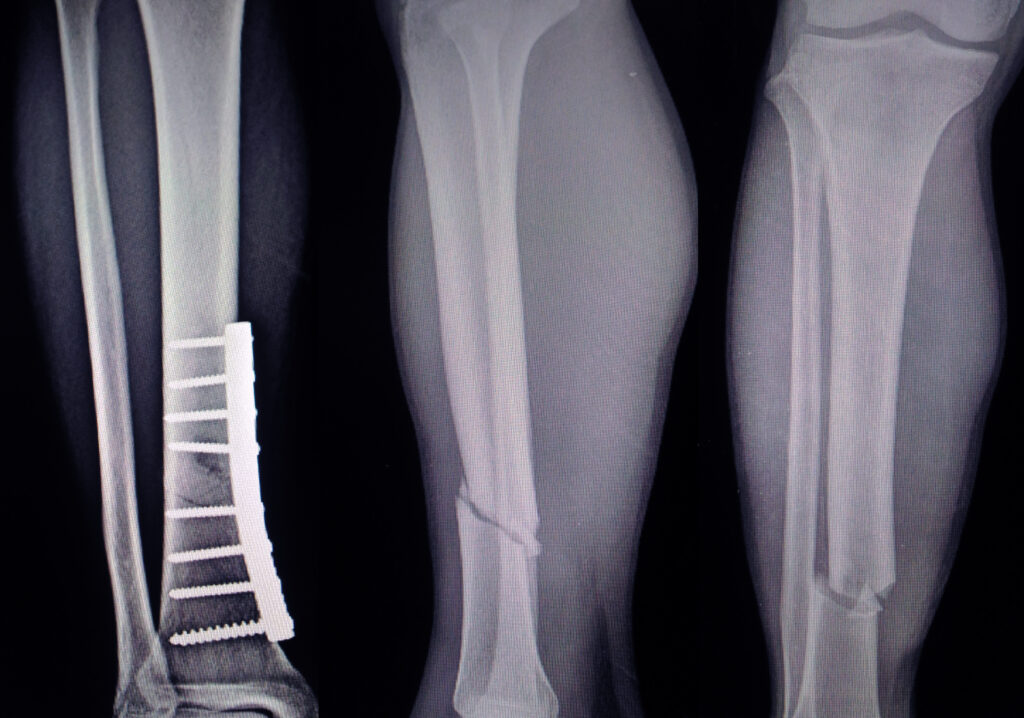

• Open Reduction and Internal Fixation (ORIF): Realigning the bone fragments and securing them with screws, plates, or rods.

• External Fixation: Using an external frame to stabilise the bone if internal fixation is not suitable.